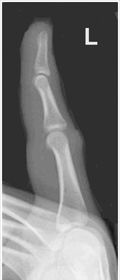

| AP Thumb Criteria | ANATOMY: entire digit including trapezium CRITERIA: equal concavity on both sides of digit open joint spaces no superimposition from adjacent bones POSITIONING: CR perpendicular @ 1st MCP joint |

| Oblique Thumb | ANATOMY: entire digit including trapezium CRITERIA: more concave to the side farthest from IR open joint spaces no superimposition from adjacent bones POSITIONING: CR perpendicular @ 1st MCP joint |

| Lateral Thumb | ANATOMY: entire digit including trapezium CRITERIA: most concave to one side, while the other is straight open joint spaces no superimposition from adjacent bones POSITIONING: CR perpendicular @ 1st MCP joint |

| AP Thumb | metacarpals overlapping thumb |

| Oblique Thumb | slightly overrotated foreshortened distal phalanx |

| Lateral Thumbs | should be concave to one side only and straight on the other images are not truly lateral |